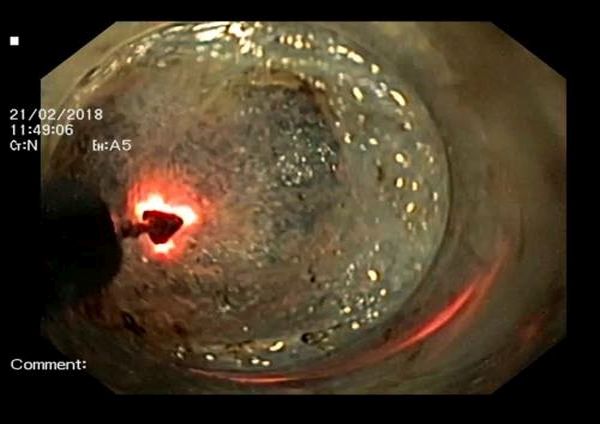

Той представи и алгоритъма на извършената операция: „За да се преодолее невъзможността да се отваря сфинктера, се прави разрез на мускулатурата на хранопровода. Инжектира се високомулекулен разтвор под лигавицата, който подува мястото, а посредством специален ток правим надлъжен разрез. През него прокарваме ендоскопа и с ножа се прави дисекция на подлигавичното пространство. Там „копаем“ тунел в стомаха, след което се разрязва мускулатурата, излиза се от тунела и първоначалният разрез се затваря с клипсове. Тази сложна и изключително прецизна интервенция позволява пациентът да се храни като всички хора.”